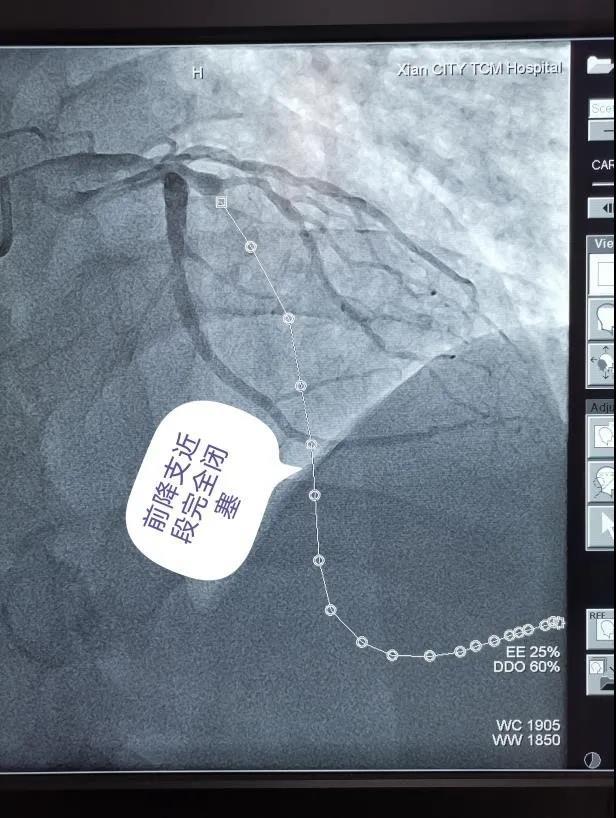

该院医务科石耀武科长指示:严格落实目前疫情防控相关规定下,启动胸痛中心救治绿色通道全力抢救患者生命。当急诊科医护转运患者至导管室时,心血管病医院介入团队和导管室已经充分做好了的术前准备。穿刺、置管,冠脉造影一气呵成,造影提示患者前降支近段完全闭塞。随后,在张拓伟副院长的指导下,刘毅龙主治医师熟练操作指引导管到位,PTCA导丝顺利通过闭塞病变,预扩张球囊扩张闭塞节段,闭塞血管前向血流恢复。

就在一切有条不紊地进行时,患者胸痛突然加重,烦躁不安,再次造影显示患者前降支血流缓慢,血压下降,波动于80/50mmHg左右,出现交界性及室性自主心律,频发室性早搏及短阵室速。经过持续大剂量泵入血管活*药性**物后患者血压仍难以维持,考虑因为心肌坏死面积大,坏死心肌水肿,心脏泵功能严重下降,血流动力学极其不稳定。张拓伟副院长果断决策,立即启用IABP(主动脉球囊反搏术)进行生命支持!

在刘毅龙主治医师的协助下,张拓伟副院长短时间顺利完成反搏球囊置入,随后韩延琪护师娴熟地完成连通管路,并精细调整反搏心电/血压触发比例,伴随着反搏气囊规律的充排气声,患者血压很快稳定在130/80mmHg左右,病情趋于平稳。随后,在张拓伟副院长的指导下,刘毅龙主治医师顺利完成后续的支架植入、高压后扩张等操作。当一条完整的血管和澎湃的血流重新呈现在眼前,患者胸痛症状完全缓解时,所有人紧绷的神经才放松下来,随后韩延琪护师根据心电/血压调整IABP的反搏触发等参数,患者病情稳定并安返病房。